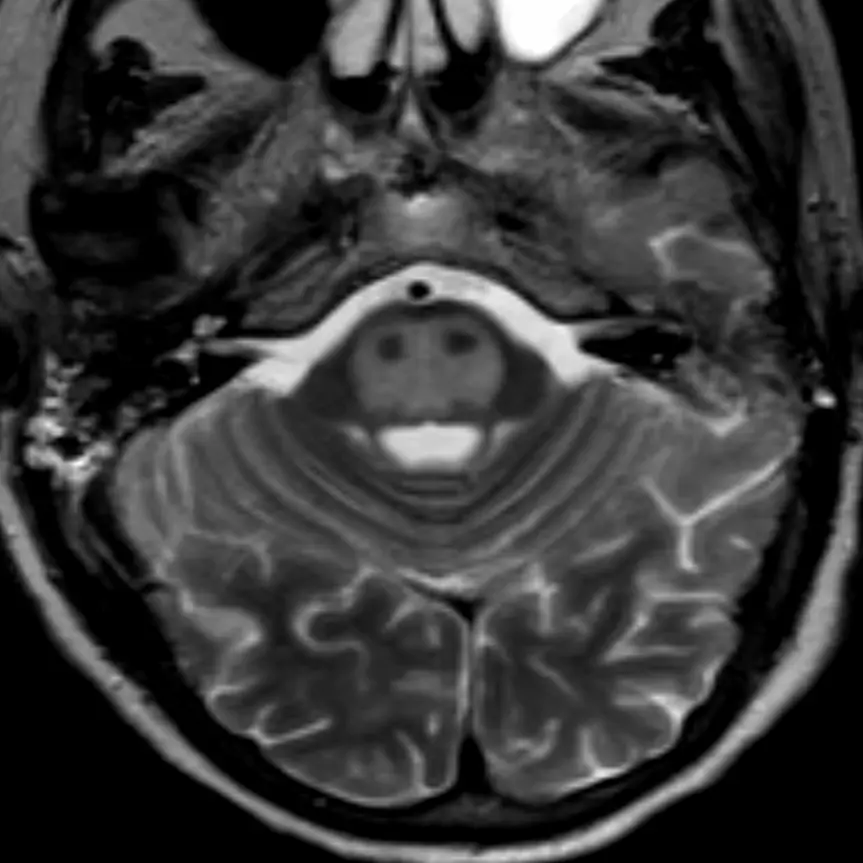

The pons' bulbous contour in the sagittal plane can also be seen on axial cuts. The "Mickey Mouse" appearance of the midbrain is no longer visible.

1. Fourth ventricle

The triangular CSF space posterior to the pons is the fourth ventricle. It should be seen on every head CT or brain MRI and, if it is not, there is likely pathology. Effacement of the fourth ventricle may be an early sign of mass effect, either due to a lesion or edema.

2. Basilar artery

The basilar artery courses along the surface of the pons. It should always be dark on a T2-weighted image. A bright basilar artery is a sign that blood has stopped moving or is moving slowly (i.e. "loss of flow void"), suggesting an occlusion.

View the images on the right to see how the caliber of the fourth ventricle changes as you scroll up and down. The fourth ventricle's caliber is largest at the mid aspect of the pons.